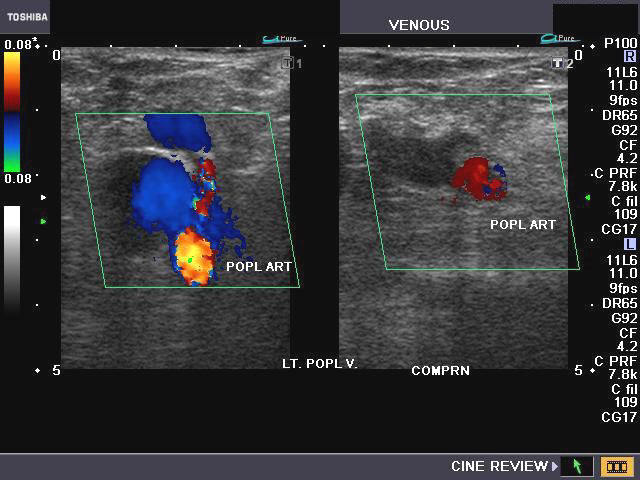

Popliteal vein thrombosis

These color Doppler ultrasound images show the left popliteal vein in an elderly female patient with marked varicose veins of both lower limbs. The most striking finding in this case, is the echogenic oval area partially obstructing flow of blood in the left popliteal vein. This color Doppler finding is typical of thrombus in the popliteal vein. Transverse section color Doppler images show failure to fully compress the affected part of the left popliteal vein, which confirms the presence of a thrombus. Note the flow of blood around the popliteal vein. (POPL Art= popliteal artery; Lt. POPL. V.= left popliteal vein).